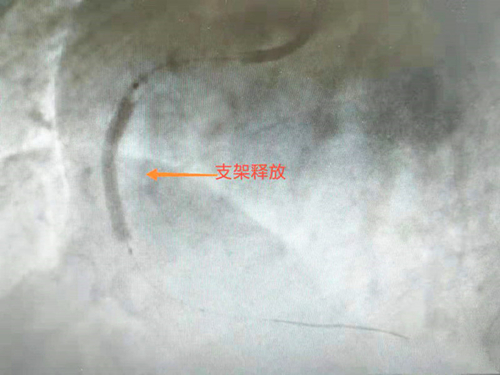

患者冠狀動脈造影提示:三支病變,前降支近段100%閉塞,回旋支近段100%閉塞,右冠狀動脈中段100%閉塞,只靠左側(cè)冠狀動脈的分支血管及側(cè)枝循環(huán)維持血液供應,右冠狀動脈是唯一的一條生命線,若此血管不開通,后果不堪設想,隨時可能出現(xiàn)心跳驟停、惡性心律失常、猝死等意外情況。手術(shù)中,患者惡心、嘔吐加重,心率、血壓持續(xù)下降,醫(yī)護人員立即給予藥物維持生命體征,并快速順利的于右冠狀動脈中段置入支架一枚。開通血管后患者疼痛癥狀緩解,心率、血壓恢復正常,直接回病房修養(yǎng)。